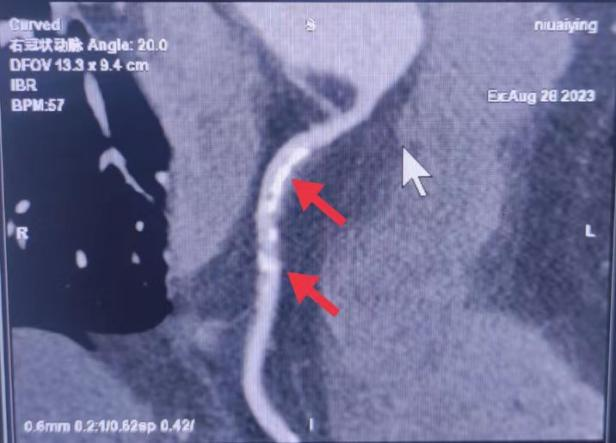

01、**女士,57岁

于2023年9月31日在邯郸仁泰东区体检。冠脉CTA检查提示:冠状动脉起源正常,分布呈右优势型。左冠主干开口正常,前降支近、中段钙化斑块,局部管腔狭窄达90%以上。右冠状动脉起自主动脉右窦,近、中、远段多发钙化斑块,局部管腔分别狭窄约56%、90%、39%左右。首次回访2023年10月8日,通知客户到三甲医院进一步检查和治疗。2023年10月24日跟踪回访,客户已在北京某三甲医院完成支架手术。